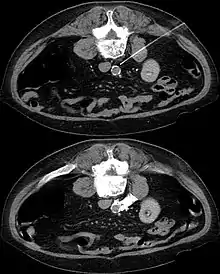

The sympathetic plexus can also be blocked in other parts of the body. Lying on the major abdominal vessels sympathetic plexus may, for example, under local anesthesia guided by a CT scan it can be turned off by injection of concentrated alcohol (interventional radiology).

In CT guided lumbar sympathicolysis, the site of neurolytic solution injection is chosen at the level of L2-L3 vertebra level. The needle should avoid the vertebral transverse process, ureter, pelvicalyceal system, and other major blood vessels. The target injection site would be anteromedial to the psoas muscle and dorsolateral to the abdominal aorta, where the sympathetic trunk would most likely be located.[1]

After the skin of the puncture site is cleaned, 2% lignocaine is injected into the to numb the skin and also the needle trajectory. Then a 22G China needle is inserted into the target site, which is bounded by the vertebral body, aorta, inferior vena cava, and psoas muscle. This region houses the lumbar sympathetic ganglion. Then, iodinated contrast medium (iohexol) and lignociane is injected into the target site to check the position of the needle tip. Once the needle tip position is confirmed, a mixture of neurolytic solution (99.9% alcohol) and iodinated contrast medium (at a ratio of 10:1) is injected into the target site.[1]